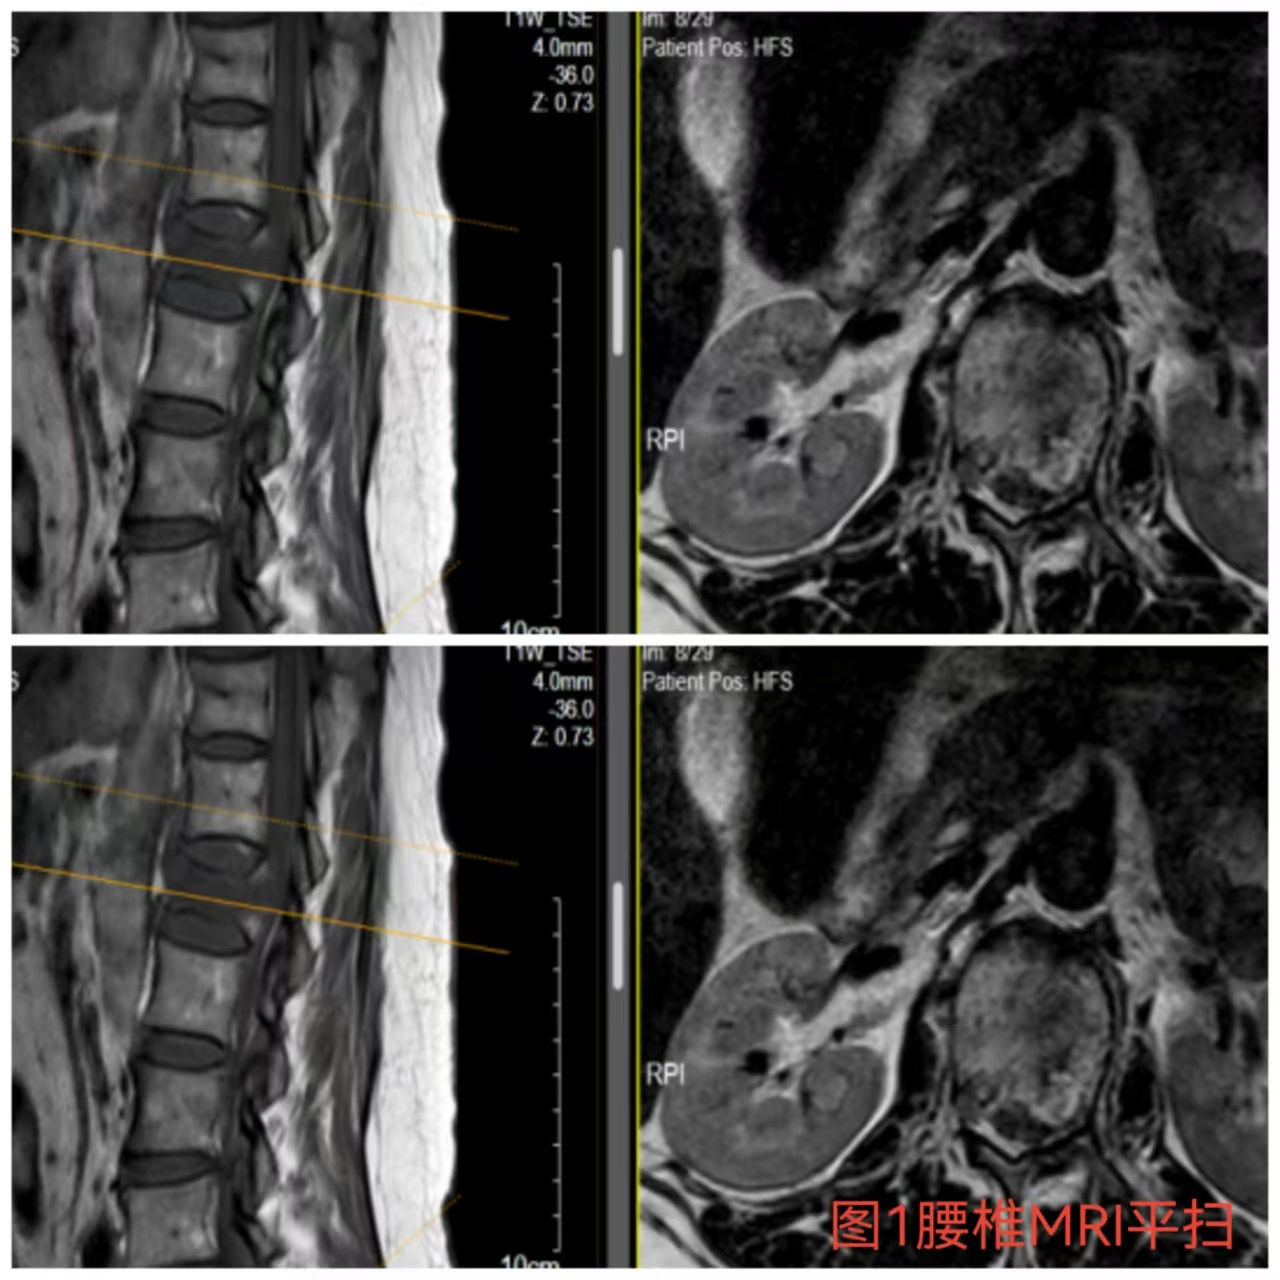

入院時患者躺在床上不能動彈,眼神中透漏著深深的無助,對于她來說這種傷情無疑是沉重的,尤其是腹股溝以下感覺消失、雙下肢肌力0級,這意味著其下肢無法活動及站立,仿佛被命運按下了暫停鍵;與病人及家屬充分溝通病情后,第一時間給予對癥治療,監(jiān)測患者生命體征,行腰椎核磁檢查(圖1)提示:腰1椎體爆裂性骨折,椎體后緣塌陷致骨性椎管狹窄,壓迫脊髓神經(jīng),結(jié)合患者病情及輔助檢查可診斷為:“L1椎體爆裂性骨折伴雙下肢截癱”。